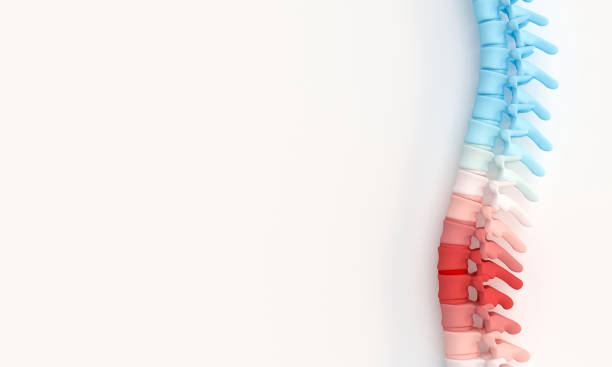

척추측만증은 초기에는 치료가 뚜렷하게 정해져 있지 않으며, 조기 발견과 조기 치료가 중요합니다. 20도 미만의 각도로 허리가 휘어진 경우에는 운동, 체조, 바른 자세 유지, 근육 강화 운동 등으로 관리할 수 있습니다. 그러나 20도 이상이 되면 더 진행될 가능성이 높으므로 보조기를 사용하거나 각도가 50도 이상일 때 허리를 교정하는 수술을 고려해야 합니다.

척추 측만증은 척추의 비정상적인 곡률로 인해 발생하는 통증이 가장 큰 증상입니다. 특히 목과 허리 부분에서 통증을 느끼는 경우가 많습니다. 이러한 통증은 일상 생활에 불편을 초래하며, 긴 시간동안 앉거나 서있을 경우 더 심해질 수 있습니다.